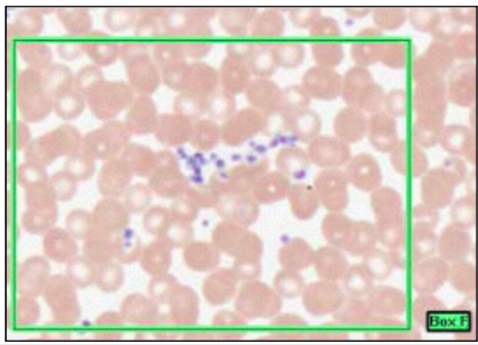

PLATELETS

- smaller than red cell

- anucleate

- fragements

- from multinuclear megakaryocytes

- blue

- 4 types of granules:

- alpha - clotting

- dense

- lysosomes

- peroxisomes - elimination of oxygen radicals